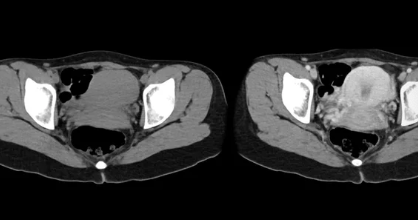

📌 4. 부신암의 진단 방법 🔍

✔ 부신암은 CT, MRI, 혈액 검사, 조직 검사 등을 통해 진단할 수 있습니다.

✅ 부신암 진단 과정

✔ 1. 혈액 검사 & 소변 검사

→ 부신 호르몬 수치 이상 확인 (코르티솔, 알도스테론, 안드로겐 등)

✔ 2. 영상 검사 (CT & MRI)

→ 부신 종양의 크기 및 전이 여부 확인

✔ 3. 조직 검사 (생검, Biopsy)

→ 종양이 양성인지 악성인지 확진

📌 TIP:

🚨 부신 종양이 4cm 이상이라면 암일 가능성이 있으므로, 정밀 검사가 필요합니다!